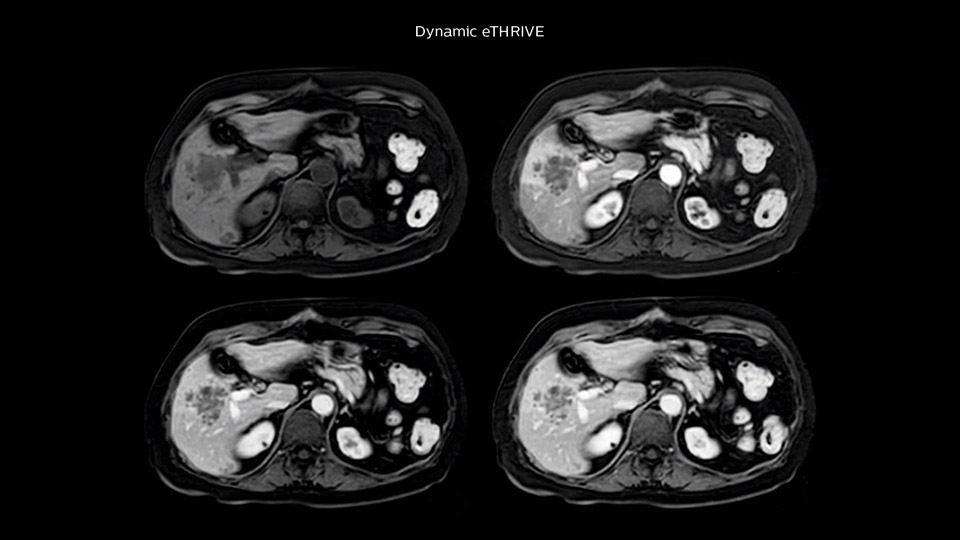

Dr. Baumann then implemented MultiVane XD for motion correction. It uses an extended reconstruction algorithm for imaging that is virtually motion free.

“With MultiVane XD we get excellent motion-corrected images with high spatial resolution. We typically first optimize our scan for high image quality, and when satisfied with that, we try to reduce the scan time. So, we combined MultiVane XD with dS SENSE, which allows us to shorten the scan time,” he explains. “The performance of MultiVane XD in liver imaging is outstanding. MultiVane XD with dS SENSE is a powerful development in improving liver image quality.”

“We include mDIXON for the dynamic sequences because of the robust and homogeneous fat suppression we get with that. We had been using eTHRIVE, but we are now quite happy with mDIXON. Sometimes we use a medication to calm the bowels, to further improve the image quality.”